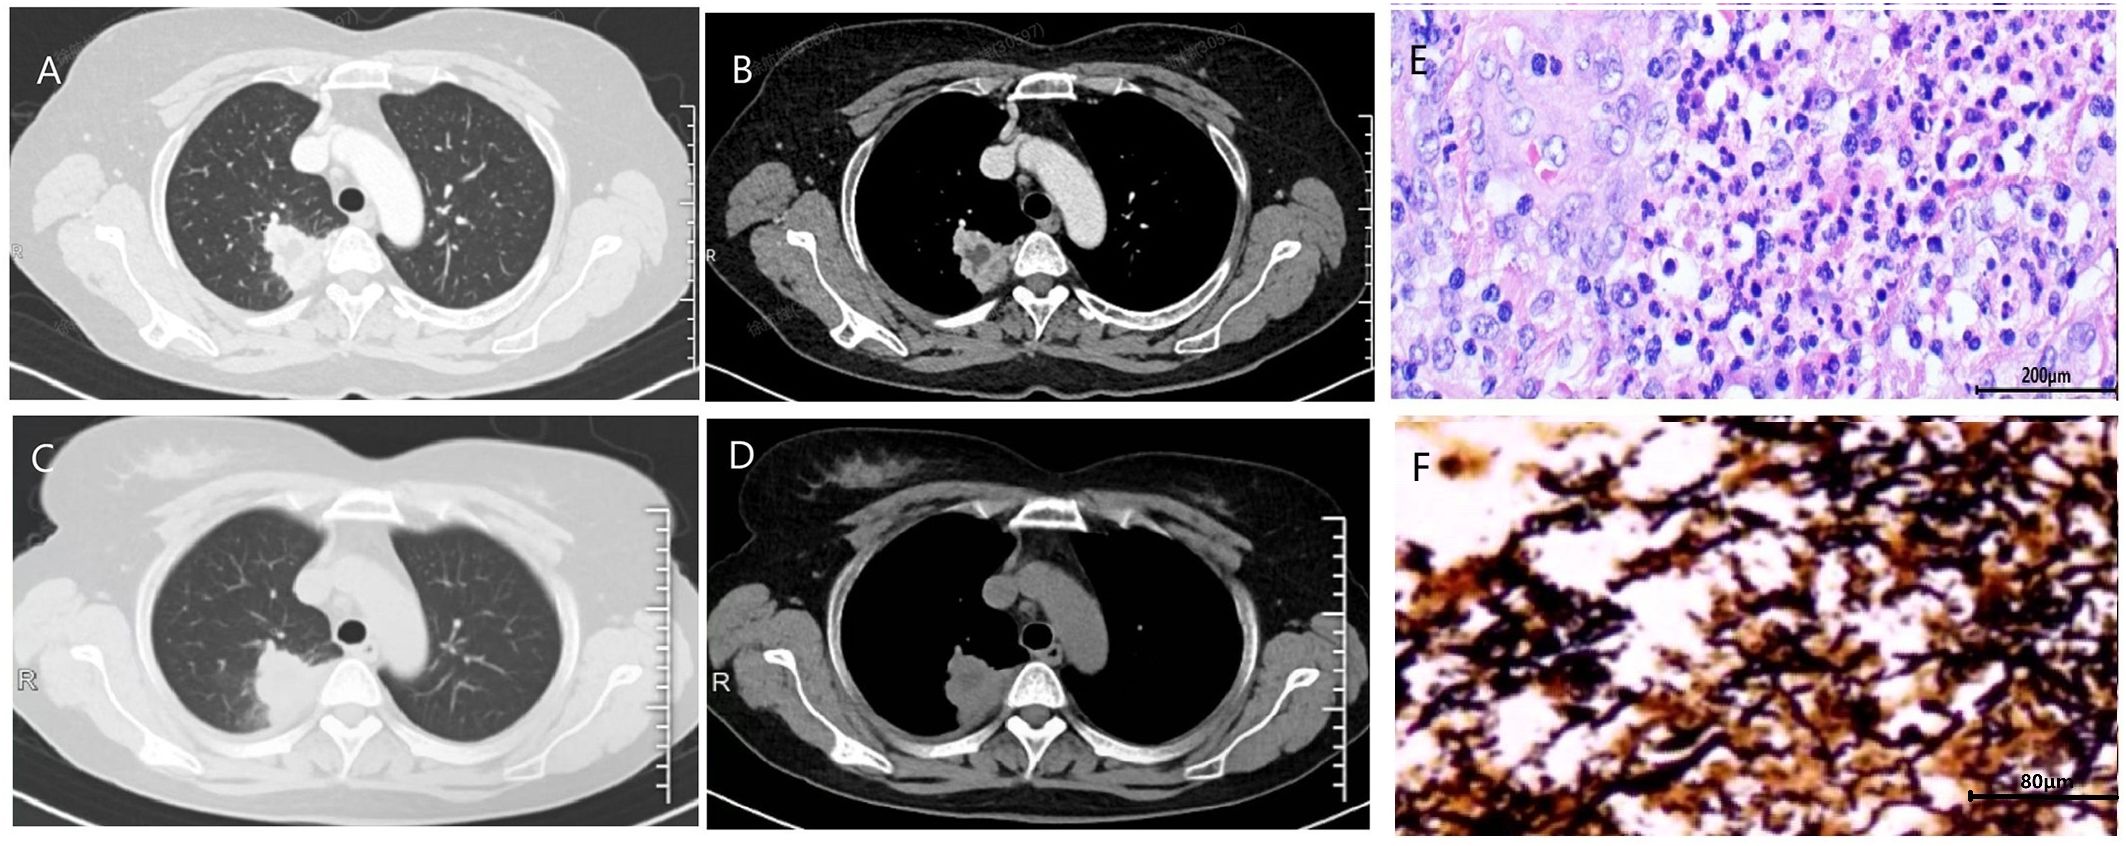

Introduction: Treponema denticola is an oral anaerobic bacterium commonly associated with periodontitis, but its role in lower respiratory tract infections (e.g., lung abscess) has long been overlooked. For bacteria that grow anaerobically, traditional culture methods exhibit low detection rates, which directly lead to the mis-diagnosis of anaerobic infection. With the ultilization of metagenomic next-generation sequencing (mNGS) in clinical practice, we studied the clinical features and treatment strategies of T. denticola-associated lung abscess. Methods: A retrospective analysis was conducted on patients confirmed with T. denticola lung abscess by mNGS from October 2023 to October 2024. Routine aerobic bacterial culture and stains were used. Histopathological analysis and Warthin-Starry silver staining was completed on samples from lung tissue. A literature review was performed using PubMed and CNKI (up to June 2025). Results: Seven patients were diagnosed with T. denticola lung abscess under mNGS. The cohort predominantly comprised elderly males (mean age 62.3 years), all of whom had underlying oral diseases. Clinical manifestations featured chronic cough (mean symptom duration 3.6 months) and frequent hemoptysis (85.7%), with notably mild systemic inflammation (only one febrile case). Characteristic CT findings included mass-like lesions with necrosis (100%) and cavitation (71.4%), without air-fluid levels. Conventional cultures were overwhelmingly negative, whereas mNGS detected T. denticola in all seven cases. Among the seven patients, one showed clinical improvement after two months of amoxicillin-clavulanate therapy, and another responded well to seven months of doxycycline treatment. The remaining five patients initially treated with levofloxacin or moxifloxacin demonstrated poor responses, with three cases ultimately requiring surgical resection of the lesions. Discussion: T. denticola lung abscess is most commonly seen in individuals with poor oral hygiene. It presents as an indolent, chronic course and a high incidence of hemoptysis. Typical CT findings include a mass-like lesion with cavitation but no air–fluid level. Traditional microbiological detection often yield false negative results, making mNGS a critical diagnostic tool. First-line therapy should include β-lactams or tetracyclines, and surgery is warranted for refractory cases or massive hemoptysis.